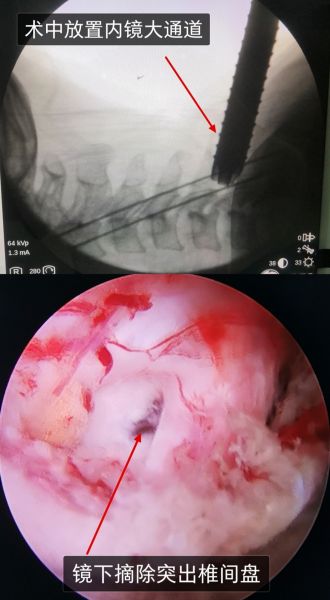

术中放置内镜通道及镜下所见

近年来,随着脊柱内镜技术的快速发展,脊柱内镜下行Key-hole术治疗神经根型颈椎病及部分脊髓型颈椎病越来越引起关注。Key-hole即“钥匙孔”技术,就是从颈后方经皮将直径0.7cm大小工作通道放入病变节段的骨面,镜下在椎板骨质上打个类似于钥匙孔的区域,经过该骨孔到达病变部位,进行病变部位突出髓核的摘除这样一种手术。镜下可以在屏幕上直视放大5倍的神经根、硬膜囊等神经结构,以及突出压迫神经的椎间盘髓核组织,在微创特制器械的帮助下,术者可安全地去除病变压迫。